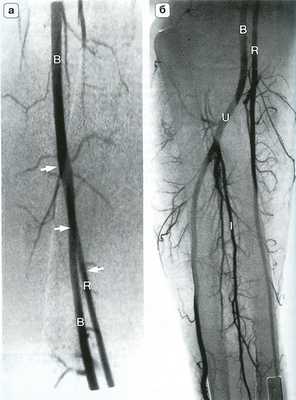

Рис. 14.4. Артериальная анатомия (а) и костные ориентиры (б) локтевого сустава. Плечевая артерия (В) делится на уровне локтевого сустава на лучевую (R) и локтевую (U) артерии. Межкостная артерия (I) является ветвью локтевой артерии, которая в некоторых случаях продолжается на кисть. RR - лучевая возвратная артерия; UR - локтевая возвратная артерия.

Рис. 14.6. Высокое отхождение лучевой артерии. На ангиограмме плеча (а) и предплечья (б) представлен вариант высокого отхождения плечевой артерии (R - стрелки) на уровне средней трети плеча. В - плечевая артерия; I - межкостная артерия; U - лучевая артерия

Рис. 14.7. Коллатеральный кровоток при окклюзии лучевой артерии. Дистальные отделы лучевой артерии (R - крупная белая стрелка) заполняются ретроградно через поверхностную и глубокую ладонную дуги (на снимке не видны). Антеградный коллатеральный кровоток осуществляется через возвратную лучевую артерию (RR - маленькая белая стрелка) и по межкостной артерии (I - маленькая черная стрелка). В - плечевая артерия; U - локтевая артерия